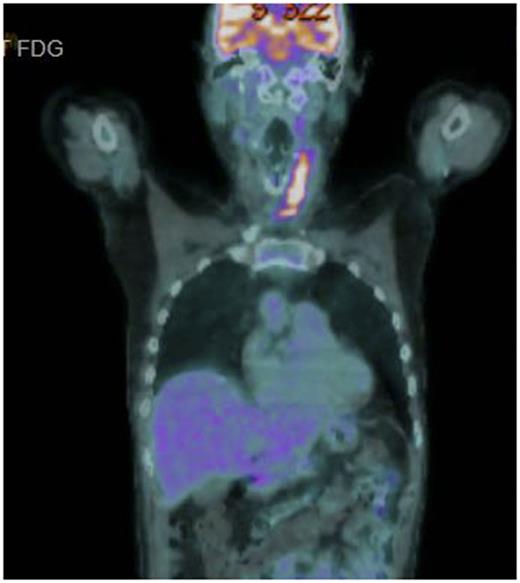

A 56 year old male presented with rapid onset superior vena cava obstruction that caused an intensive care admission at the time of diagnosis. Staging showed stage 2 with neck disease, near complete SVC obstruction and a 6 x 5 x 5cm superior mediastinal mass. Therapy was commenced with R CODOX-M / R IVAC with an initial symptomatic improvement but by the time of recovery from course 2, the symptoms of respiratory distress were recurring in the left neck where partial acute respiratory obstruction occurred. No significant improvement in the neck mass was seen on repeat CT and urgent radiotherapy (R/T) was given to relieve symptoms. Persistent active disease was then confirmed by CT /PET scanning in the left neck (SUV 10.8), an exemplar image of this scan is shown in Figure. The patient was counselled as to the dire prognosis but was unwilling to accept that further intensive treatment was unlikely be successful and requested further chemotherapy. In the light the intensity of the treatment already delivered a novel strategy was conceived and agreed.